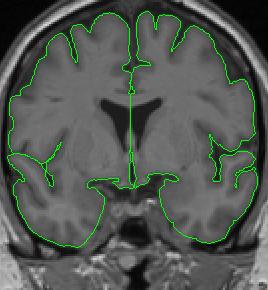

Anteriorly, when the temporal lobes are present but not connected to the frontal lobes, the temporal lobes are extracted separately from the frontal lobes. Thus, you will have four separate outlines that make up the cerebral exteriors.

cerebral exterior 3

At the fronto-temporal junction, if the contour encompasses the entire hemisphere but the white matter between the lobes is not continuous, it is necessary to separate the frontal and temporal areas. Each hemisphere and lobe should then be extracted independently.